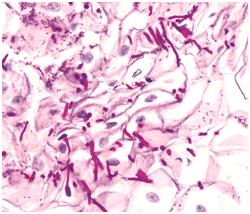

Figure 1 Candida pseudohyphae and yeast forms with inflammatory cells- aspiration cytology.

Acute candidiasis: The distinguishing aspect is the presence of neutrophils in the stratum corneum. Disseminated disease expounds dermo-epidermal inflammatory infiltrate with intra-epithelial micro-abscesses.1,5 Fungal components are infrequent. Periodic acid Schiff(PAS), Silver Methanamine (Grocott stain- black fungal hyphae with a green environment and is specific for the deteriorating fungus ) aids in delineating the organism.1,5

Molecular analysis of Candida employs a Real time Polymerase Chain Reaction (RT-PCR). Monoclonal antibodies besides the Rapid agglutination tests (RLA) may also be applicable. Debatable conditions such as a “Candida Leukoplakia” mandate an evaluation of a histological specimen.1,6 Imprint smears and tissue material may be analyzed with the Periodic acid Schiff’s (PAS) stain. The carbohydrates in the fungal cell wall stain magenta. Gram Positive reactivity on Gram’s stain may be elucidated by the micro-organism.1,2,5